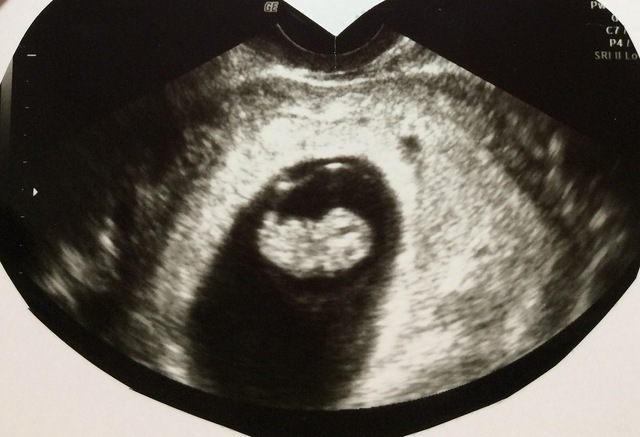

8週3日(8w3d・男の子)|ちゃるてぃく さん(31歳)

エコー写真撮影時のエピソード:はじめての妊娠で、お腹に本当に赤ちゃんがいるのか不思議な感じで毎日過ごしてたところ、こんなベストショットが撮れました。一気にテンション上がったのを覚えてます。その後あと2人妊娠、出産しましたが、後にも先にもこんなベストショットは撮れませんでした。